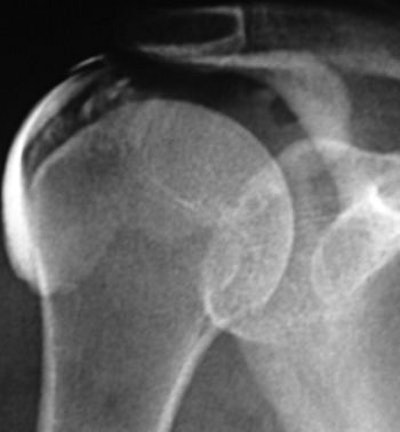

![]() |

| A 46-year-old woman with inflammatory changes in acromioclavicular joint with osteophyte formation, secondary impingement, and bursitis (grade 2). Symptom duration was four months, and patient reported complete resolution of symptoms after six months of follow-up. Subacromial bursogram shows inflammatory changes in acromioclavicular joint. |

| Same patient as above. Symptom duration was four months, and patient reported complete resolution of symptoms after six months of follow-up. Coronal oblique STIR MR image (TR/TE, 2,000/20; inversion time, 160 msec; echo-train length, 8) shows changes in acromioclavicular joint (open arrow) with osteophyte formation (closed arrow). Hambly N, Fitzpatrick P, MacMahon P, and Eustace SW, "Rotator Cuff Impingement: Correlation Between Findings on MRI and Outcome After Fluoroscopically Guided Subacromial Bursography and Steroid Injection" (AJR 2007; 189:1179-1184). |